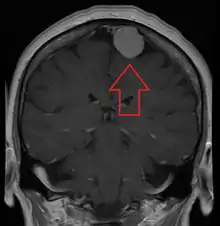

MRI image of a meningioma with contrast

Meningiomas are visualized readily with contrast CT, MRI with gadolinium,[22] and arteriography, all attributed to the fact that meningiomas are extra-axial and vascularized. CSF protein levels are usually found to be elevated when lumbar puncture is used to obtain spinal fluid. On T1-weighted contrast-enhanced MRI, they may show a typical dural tail sign absent in some rare forms of meningiomas.[17]